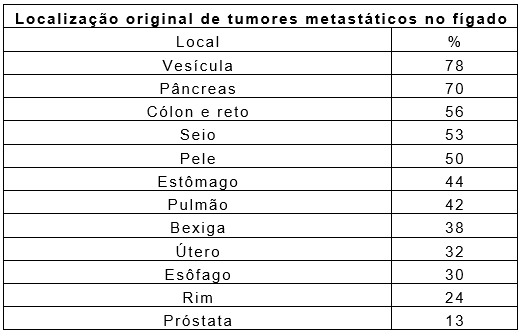

METÁSTASES HEPÁTICAS

Pela sua posição estratégica e para cumprir suas funções, o fígado recebe sangue diretamente de diversos órgão e indiretamente de todo o organismo. Por esse e outros motivos, é nele que grande parte das células cancerosas de outras partes do organismo, que caem na circulação sanguínea, acaba se alojando e produzindo um novo tumor. Esse novo tumor é chamado de metástase.

O diagnóstico de uma metástase hepática pode ser realizado durante a investigação de um tumor em outros órgãos, ou pode ser a primeira manifestação de um câncer de outra localidade. Em alguns casos, apenas a metástase hepática é descoberta e a localização inicial do tumor permanece desconhecida.

As metástases ocorrem de tumores altamente malignos, podendo acometer vários órgãos concomitantemente. No fígado, as lesões tendem a ser maiores e múltiplas, levando à destruição hepática. Por esse motivo, os sintomas iniciais podem ser os mesmos de uma cirrose hepática severa.

O tratamento é muito variado dependendo do tipo de tumor e a sua origem. De modo geral, o tratamento é cirúrgico ou quimioterápico, reservando-se outros procedimentos como os percutâneos apenas para casos excepcionais.